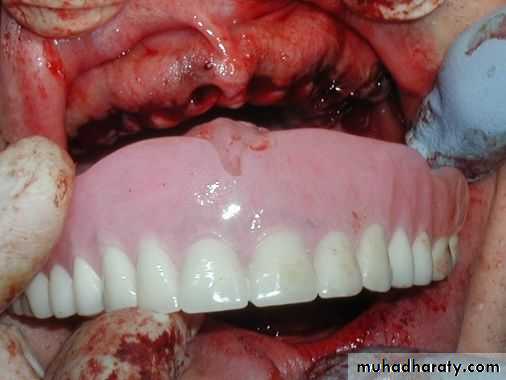

(4) Insertion of the clear acrylic template to check if bone removal has been sufficient. Blanching of the mucosa is clearly seen beneath the template in any area where there is excessive pressure.

(5) Suturing of the sockets and insertion of the immediate denture.

Tooth set up and try in Extraction and insertion